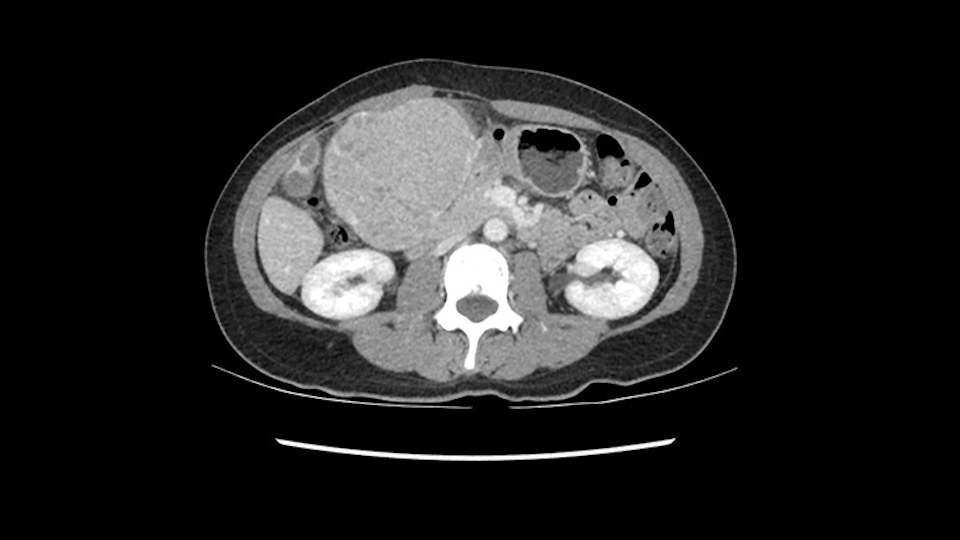

When you see the axial sections of the scan, you find it's a largely exophytic mass and its well-encapsulated. So this is typically true of a well-differentiated hepatocellular carcinoma. If you look at this, this is the gallbladder which is being displaced to the right and the mass is in the Sg4 of the liver, exophytic, projecting down. As it is coming down, it is also displacing the duodenum and the head of the pancreas which is being pushed towards the left and it's going right up to the cava, the start of the anterior surface of the cava. Obviously getting a lot of collaterals and vascularity from all the vessels around but one has to be very careful in evaluation of the main portal pedicle in this particular case and of course arterial inflow to the Sg4 and of course the left lobe of the liver.

The cava however is again displaced by this well encapsulated mass, so I would expect that I should be able to lift out of the cava with some moment of careful dissection and the cava is not infiltrated by this tumor. Most of the tumor is below the portal plane and the hepatic-venous vein is completely free. You have the left and the middle hepatic vein joining together and opening up. The right hepatic vein is as usual. All the superior segments of the liver are intact so we do not expect any major problem in this particular case as far as the venous outflow is concerned. So this is about the preoperative planning as far as this case is concerned.

So in planning for this operation, as I look at the scans, I first visualize the arterial phase and I can see that there’s are a lot of big feeding arteries to this large tumor. Likely all the right side vessels feeding the right side of the liver: right hepatic artery and likely the Segment 4 artery are spared from the tumor. It’s likely the left hepatic artery is ramificating and giving feeding arteries to this tumor. It certainly looks like a large mass that its compressing other structures like the cava, the pancreas, the stomach; but I think there’s a plane and we can see that better in the venous phase. There’s a plane of separation between the gallbladder, the pancreas, the cava, that this tumor is abrupting but likely not invading. Usually, these masses actually don’t invade at that level and basically are pushing the tissues and once you open, you’re able to separate the tumor. Sometimes there’s some adhesions but you can actually separate and there’s usually no invasion.